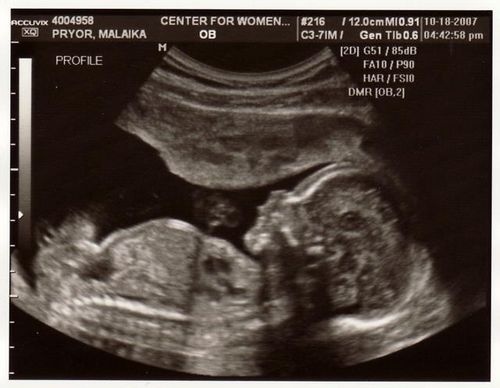

Реальний термін уточнюється на всіх сеансах УЗД, особливо перших триместрів. В процесі діагностики вимірюються окремі частини тіла плода, їх довжина, окружності і співвідносяться з таблицями розвитку. Метод УЗД, особливо на ранніх термінах, є найбільш достовірним індикатором.

Перше роблять в рамках комплексного обстеження, яке повинно виявляти грубі хромосомні, генетичні патології і дефекти анатомічної будови плоду. Його виконують в період з 11 по 14 тиждень.

Що роблять в рамках першої діагностики стану плодового яйця методом УЗД?

- Виявляють нормальну вагітність, при цьому виключають позаматкову,

- Уточнюють термін вагітності в тижнях,

- Виявляють грубі пороки серця плоду,

- Перевіряють наявність внутренніхорганов (печінки, шлунка, органів черевної порожнини),

- Вимірюють основниескелетно-м'язові розміри, такі як БПР, КТР,

Перше ультразвукове дослідження - це джерело цінної інформації про те, як сформувалося плодове яйце і «дитяче місце», одне з найбільш важливих обстежень раннього періоду. Отримана до 14 тижнів інформація на основі першого УЗД, укупі з аналізами крові, дозволяє приймати рішення про продовження виношування вагітності або переривання.